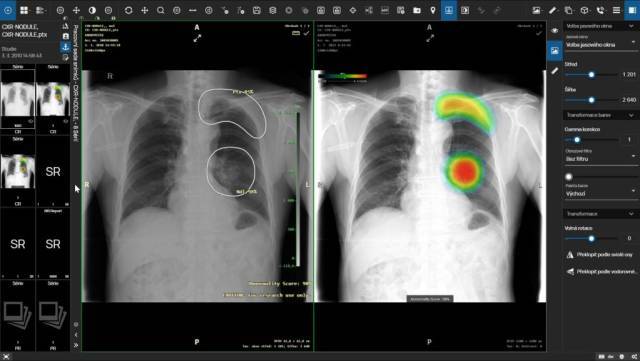

AI má v dnešnej dobe využitie v rôznych oblastiach. Napríklad pri diagnostike pľúcnych ochorení ako je edém či tuberkulóza môžu pomôcť riešenia vyhodnocujúce röntgen pľúc, iné AI riešenia, ktoré sú schopné vyhodnocovať CT pľúc, môžu byť nápomocné pri identifikácii pľúcnych nodulov, teda oblastí značiacich prvopočiatok malígneho ochorenia. Röntgen končatín je možné zanalyzovať pomocou AI a identifikovať tak fraktúru, dislokáciu alebo kĺbny výpotok. Analýza CT mozgu s využitím AI zase pomôže s diagnózami ako je fraktúra lebky či krvácanie. Ďalšie uplatnenie AI nájdeme v mamografii pri detekcii a klasifikácii mikrokalcifikácií alebo hodnotení hustoty pŕs pomocou stupnice BI-RADS. Rovnako je možné využiť AI pri príprave merania – klasifikácia skoliózy, náklon pánvy, dysplazia bedrového kĺbu. V oftalmológii vie AI pomôcť s diabetickou retinopatiu, glaukomom (zeleným zákalom) či vekom podmienenou makulárnou degeneráciou (AMD). Dôležité vo všetkých prípadoch je, aby využívané riešenia boli certifikované ako zdravotnícky prostriedok a odpovedali novému nariadeniu o zdravotníckych prostriedkoch MDR.

Zamýšlali ste sa nad tým, kde je vlastne AI inštalovaná, keď ju chce nemocnica využívať? Väčšina dodávateľov umožňuje oba spôsoby, teda inštaláciu on-premise (tj. vo vlastnej infraštruktúre nemocnice) aj inštaláciu v cloude, pričom práve cloudy sú využívanejšie. Zároveň ale platí aj to, že cloudy sú zraniteľnejšie. V tomto prípade je treba dbať na zvýšenú bezpečnosť, šifrovanie komunikácie a anonymizovanie dát, ktoré opúšťajú prostredie nemocnice. Zároveň by malo byť dané riešenie AI umiestnené v cloude v rámci Európskej únie. Pri výbere AI je dobré sa uistiť, či výrobca svoje riešenie penetroval a realizoval skúšky s cieľom identifikovať zraniteľnosti svojho systému voči útoku hackerov. Samostatnú kapitolu tvoria aj inštalácie AI do prostredia nemocnice štýlom „tak, ako prídu“, niektoré AI môžu byť využívané na modalite, iné sú do nemocnice nainštalované samostatne bez súčinnosti dodávateľov aktuálne využívaných nemocničných systémov a bez integrácie do jednotného používateľského prostredia. Nemocnice by sa teda mali brániť nekoordinovanému zavádzaniu rôznych AI technológií od rôznych dodávateľov a mali by k tejto problematike pristupovať systematicky a s ohľadom na bezpečnosť pacientskych dát. Výsledky analýz rôznych AI by sa naviac mali používateľom zobrazovať jednotným spôsobom bez ohľadu na to, z akej umelej inteligencie pochádzajú. Ideálnym východiskom z tejto situácie je integrovať riešenia AI do jedného systému, napríklad PACS (systému na archiváciu a zobrazovanie obrazovej dokumentácie), s ktorým pracuje každý rádiológ. Výhodou tohto konceptu je, že komunikáciu s cloudami a riešeniami AI potom zabezpečuje jeden systém z nemocnice a používateľ pracuje s jedným systémom, resp. jedným prostredím. Výsledky rôznych dodávateľov AI sú tak tiež zobrazované pre používateľa v jednotnej forme.